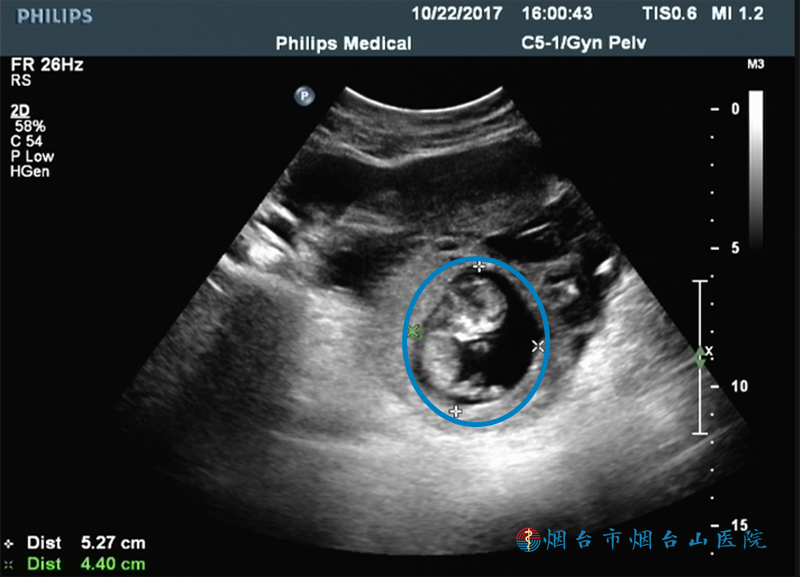

前段时间,徐女士感觉有些腹痛、腹胀,便到烟台山医院消化内科请大夫看了一下,被告知她的消化系统没啥事儿,因为她有合并贫血的症状,大夫建议她到妇科就诊,“患者在我们医院做了一个超声检查,检查发现,她的子宫右后方有一个不均质回声团块,内见孕囊回声,囊内见一胎儿,头臀长约4.5厘米,可见胎心搏动。”烟台山医院妇科主治医师张璐表示,这些情况表明患者为宫外孕,“接诊后,我们立即为患者安排了急诊手术,手术过程非常顺利,术后,患者恢复得也很好。”

超声检查显示:患者子宫右后方有一个不均质回声团块,内见孕囊回声,囊内见一胎儿,可见胎心搏动

张璐说,腹腔妊娠是一种比较凶险的宫外孕。期间,孕妇通常出现过比较明显的腹痛和阴道流血,随着胎儿长大,阴道流血逐渐消失。该患者恰巧在一月前出现过腹痛和阴道流血,误以为是月经期痛经,此后,间歇性出现过少量阴道流血,但没引起重视。腹腔妊娠的胎儿很难足月成活,因此,一经发现,需尽快手术取出胎儿,“术中发现腹腔内有积血及血块约1000毫升,胎儿及胎盘均位于输卵管外,胎盘‘扎根’在输卵管伞和输卵管右后方的盆腔腹膜上,胎儿的头臀长约5厘米。”